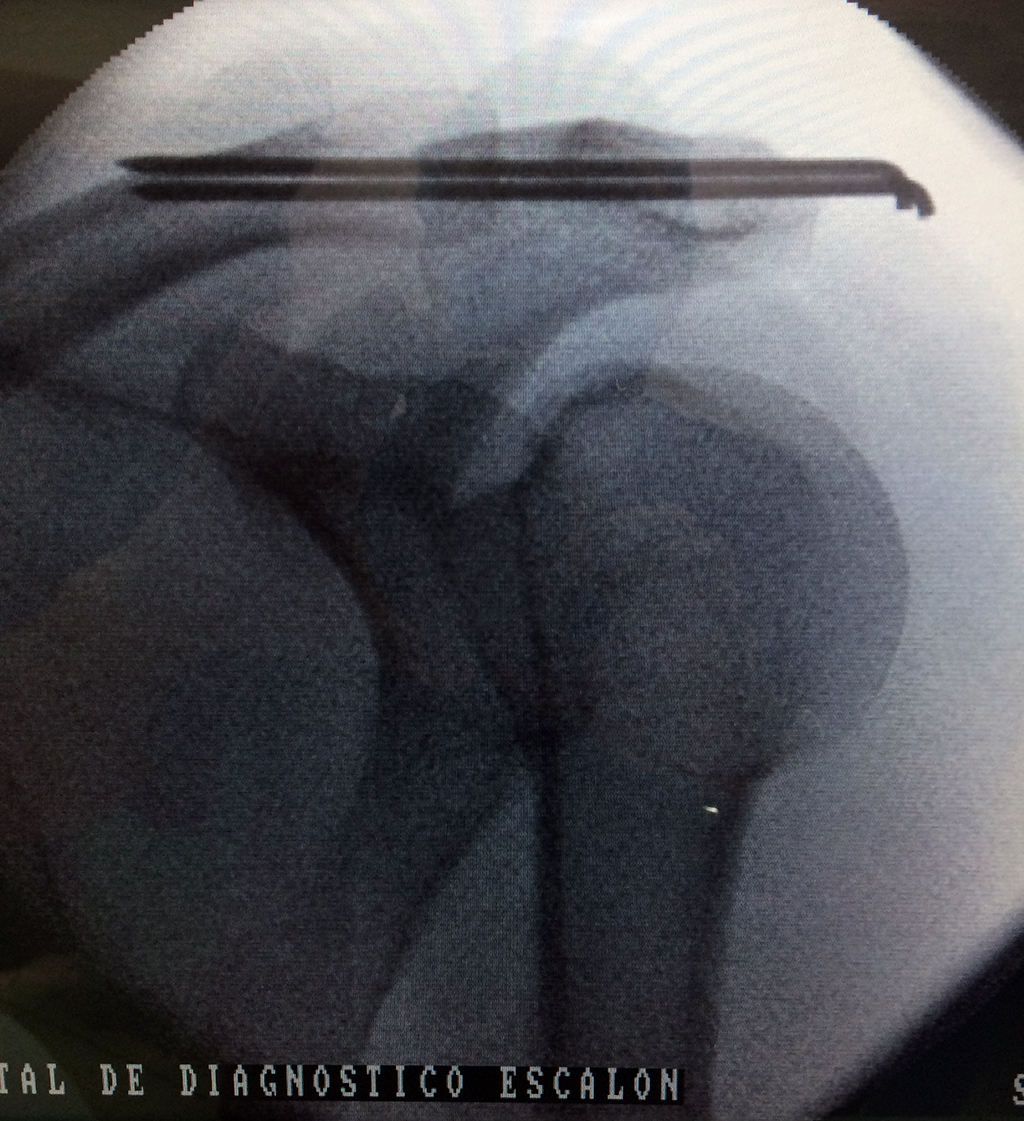

Cirugias en El Salvador - Clavícula

La clavícula es un hueso largo, con forma de "S" itálica, situado en la parte anterosuperior del tórax. Junto con la escápula forman la cintura escapular. Se puede palpar por toda su longitud y se extiende del esternón al acromion de la escápula, siguiendo una dirección oblicua lateral y posterior.